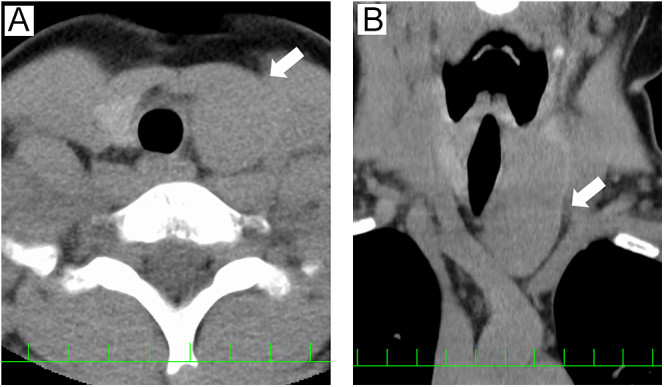

Summary: Spindle epithelial tumor with thymic-like elements (SETTLE) is an extremely rare tumor that occurs primarily in the thyroid gland. Histologically, SETTLE is characterized by the presence of spindle-shaped epithelial cells and glandular structures. However, it is known that diagnosis via fine-needle aspiration cytology can be challenging. SETTLE predominantly occurs in younger individuals and has a less favorable prognosis compared to differentiated thyroid carcinoma. Therefore, ensuring accurate diagnosis and appropriate treatment is crucial. We encountered a case of spindle epithelial tumor with thymus-like differentiation in a 10-year-old patient for whom the preoperative diagnosis was successfully established through fine-needle aspiration cytology, which facilitated appropriate surgical resection. Comprehensive histopathological examination and immunohistochemical analysis are essential to ensure appropriate management and surveillance of SETTLE.

Learning points: A rare thyroid tumor, spindle epithelial tumor with thymic-like elements (SETTLE), was diagnosed preoperatively and treated surgically. SETTLE presents with characteristic histological features that must be recognized for accurate diagnosis. In addition, diagnosis through cytology is often challenging. The primary treatment for SETTLE is surgical intervention as radiotherapy and pharmacological treatments are generally not expected to be highly effective. Radical resection is the only effective treatment, making the selection of the surgical procedure according to the stage of the disease essential.